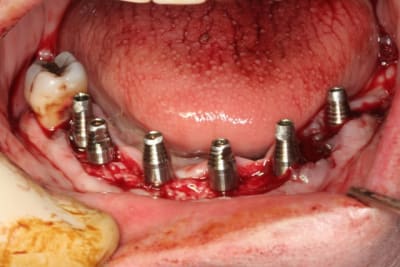

bon, et bien c'est fait!

durée...de 9h30 à 17h30...çà c'est assez épuisant...

ah, oui, j'allais oublier au maxillaire 8 legacy3 diamètre 3.7mm et en 13 de long (sauf 22 en 11.5mm)

mandibule 6 implants de 13mm et 3.7mm de diamètres (sauf 36 et 45 en 4.2mm/13)